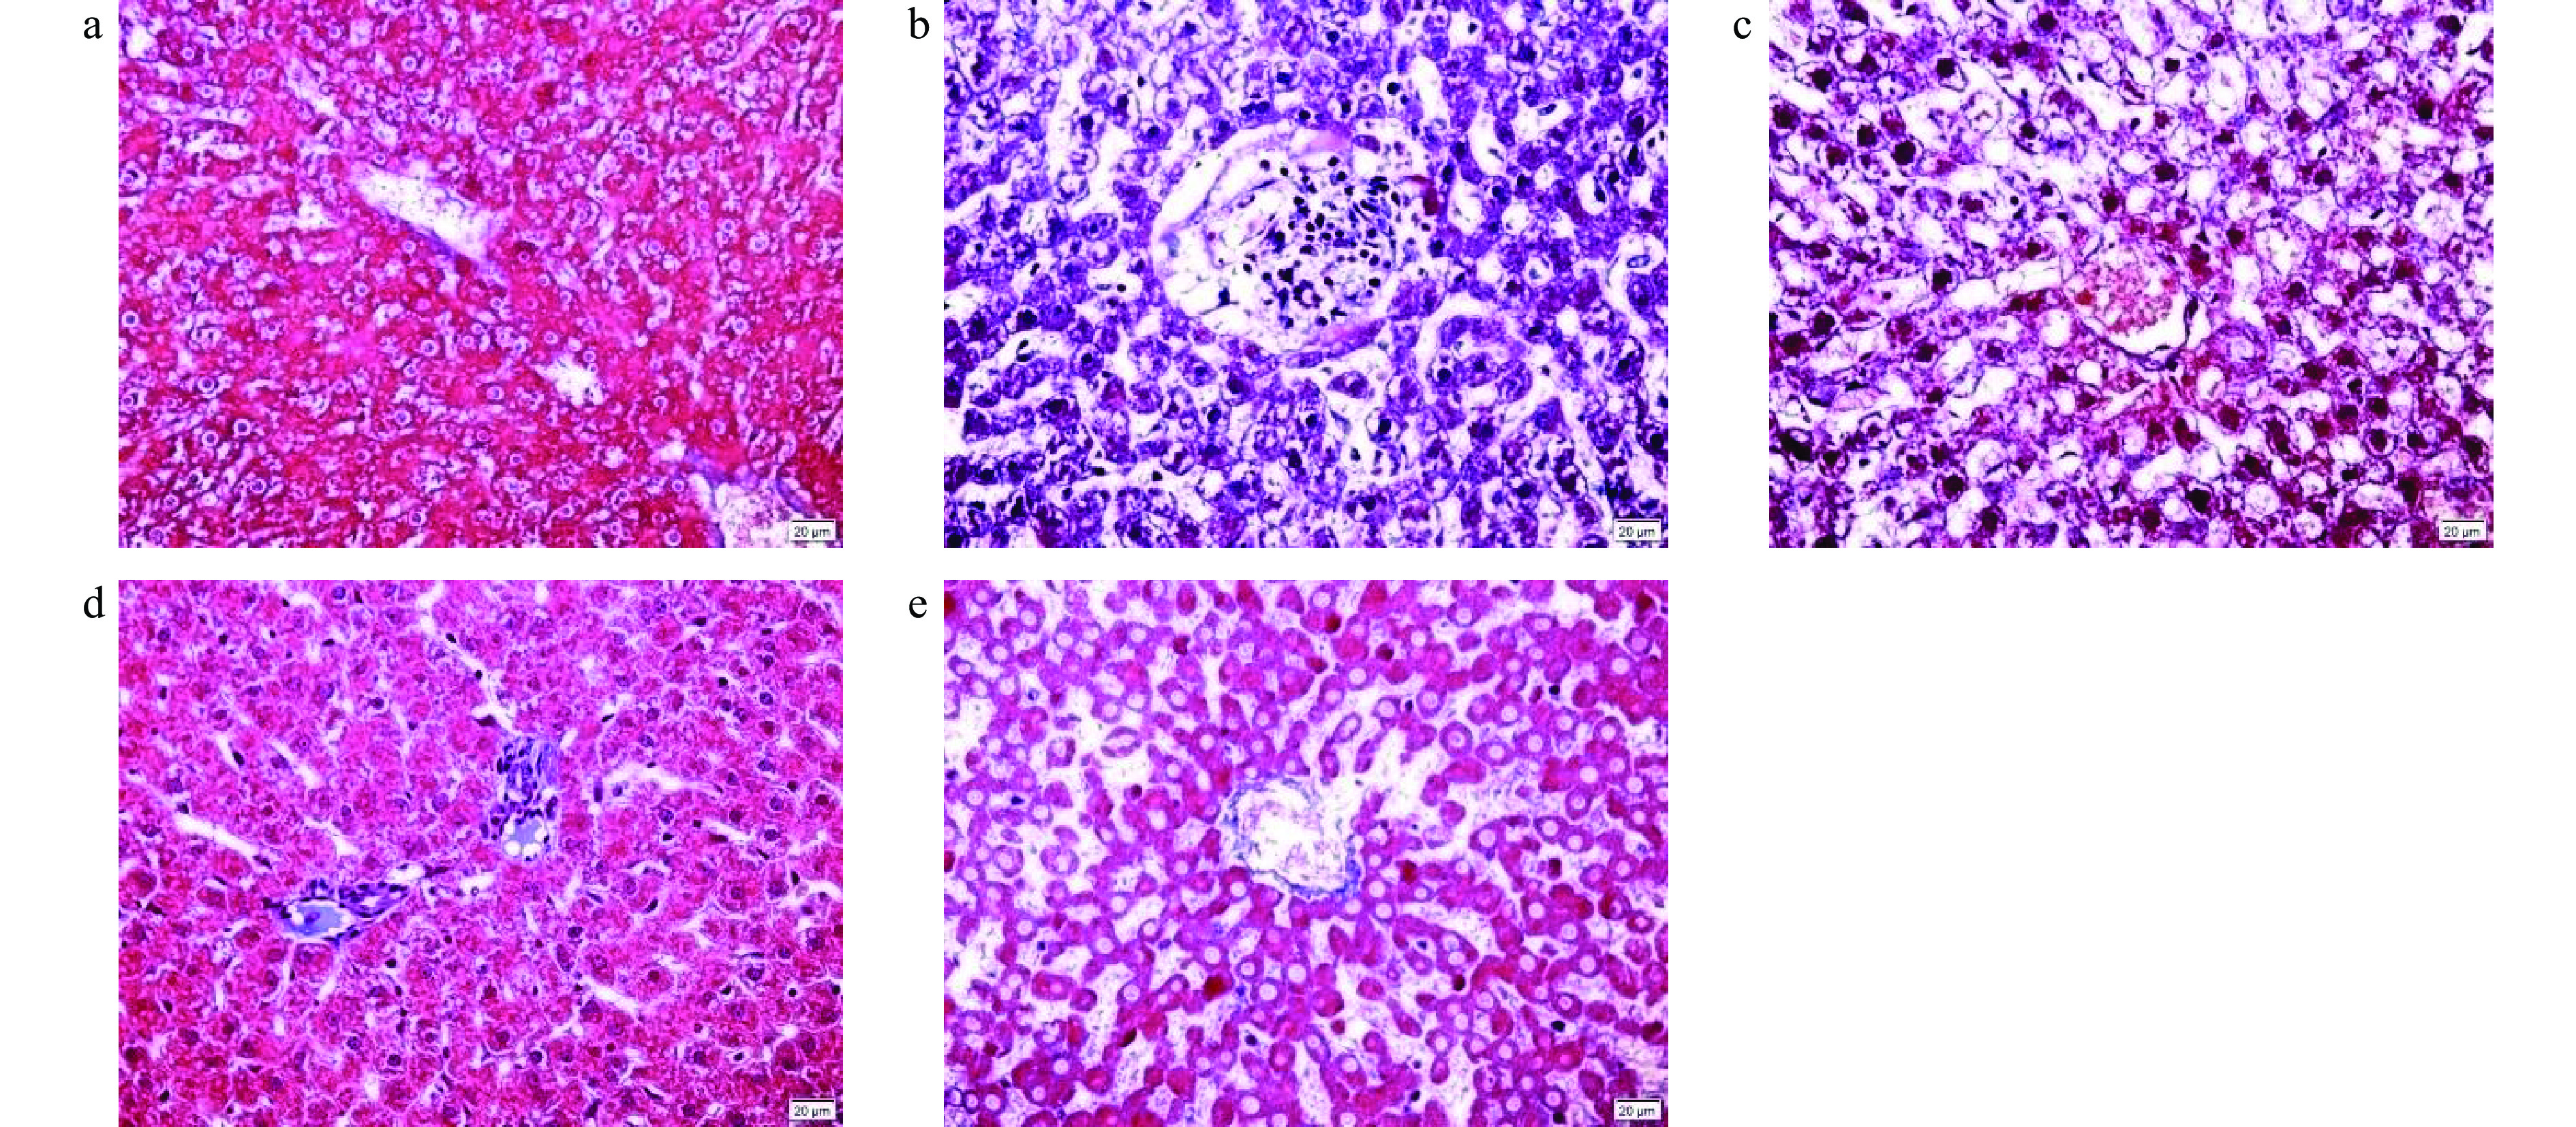

• 摘要: 目的:探讨白芍总苷(total glucosides of paeony,TGP)对大鼠高尿酸血症并发肝脏损伤的保护作用。方法:将50只雄性Sprague-Dawley大鼠随机分为5组:正常组、模型组、TGP低剂量组(100 mg/kg)、TGP高剂量组(300 mg/kg)和别嘌醇组(27.0 mg/kg),每组10只。模型组、TGP低、高剂量组和别嘌醇组大鼠分别按照1.5 mL/100 g的体积灌胃腺嘌呤6.66 mg/mL+氧嗪酸钾100 mg/mL的混合液制造高尿酸血症大鼠模型,每日7:00和20:00各1次,持续3周。每日12:00按剂量分别灌胃给药TGP和别嘌醇,持续5周。5周后,处死大鼠,检测各组大鼠的肝脏脏器指数,血清中总胆固醇(total cholesterol,TC)、甘油三酯(triglyceride,TG)、丙二醛(malondialdehyde,MDA)、超氧化物歧化酶(superoxide dismutase,SOD)、谷草转氨酶(aspartate aminotransferase,AST)、谷丙转氨酶(alanine aminotransferase,ALT)、尿酸和黄嘌呤氧化酶(xanthine oxidase,XOD)等生化指标,同时对肝脏进行病理切片观察。结果:高、低剂量TGP均能极显著增加高尿酸血症大鼠的肝脏脏器指数(P<0.01)。低剂量TGP显著降低了高尿酸血症大鼠血清中的MDA水平(P<0.05)和尿酸水平(P<0.01),升高了SOD(P<0.01)水平。高剂量TGP显著降低了高尿酸血症大鼠血清中的ALT(P<0.05)、尿酸(P<0.01)和XOD水平(P<0.05),升高了SOD水平(P<0.01);病理观察发现,高剂量TGP能缓解高尿酸血症大鼠肝细胞脂肪变性、肝细胞周围纤维化和尿酸盐结晶沉积。结论:TGP能显著改善高尿酸血症大鼠肝细胞的氧化损伤和肝脏病理损伤,从而对高尿酸血症并发肝脏损伤有一定的保护作用。

Abstract: Objects: To investigate the protective effect of total glucosides of peony (TGP) on rats with hyperuricemia and liver damage. Methods: Fifty male Sprague-Dawley rats were randomLy divided into 5 groups: The normal group, the model group, the TGP low dose group (100 mg/kg), the TGP high dose group (300 mg/kg) and the allopurinol group (27.0 mg/kg), with 10 rats in each group. The hyperuricemia rat model was established by gavage of adenine 6.66 mg/mL+oteracil potassium 100 mg/mL suspension (1.5 mL/100 g) in the model group, TGP low dose group, TGP high dose group and allopurinol group respectively, once respectively of 7:00 and 20:00, continues for 3 weeks. TGP and allopurinol were intragastrically administered at 12:00 every day, and continues for 5 weeks. After 5 weeks, the rats were sacrificed. The liver organ index was measured, the content of serum total cholesterol (TC), triglyceride (TG), malondialdehyde (MDA), superoxide dismutase (SOD), uric acid and xanthine oxidase (XOD) were measured, and the activity of aspartate aminotransferase (AST), alanine aminotransferase (ALT) in serum were measured. At the same time, pathological changes of the liver were observed. Results: Both the high and low doses of TGP significantly increased the liver organ index of hyperuricemia rats (P<0.01). Low dose TGP decreased the level of MDA (P<0.05) and significantly decreased the level of uric acid (P<0.01), significantly increased the levels of SOD (P<0.01) in serum of hyperuricemia model rats. High dose TGP decreased the levels of ALT (P<0.05) and XOD (P<0.05), significantly decreased the level of uric acid (P<0.01), significantly increased the level of SOD (P<0.01) in serum of hyperuricemia model rats. Pathological observation showed that high dose TGP alleviated hepatocyte steatosis, perihepatocyte fibrosis and urate crystal deposition in hyperuricemia rats. Conclusion: TGP would have a good hepatic protective effect during hyperuricemia through significantly improveing the oxidative damage and liver pathological damage of hepatocytes in hyperuricemia rats.